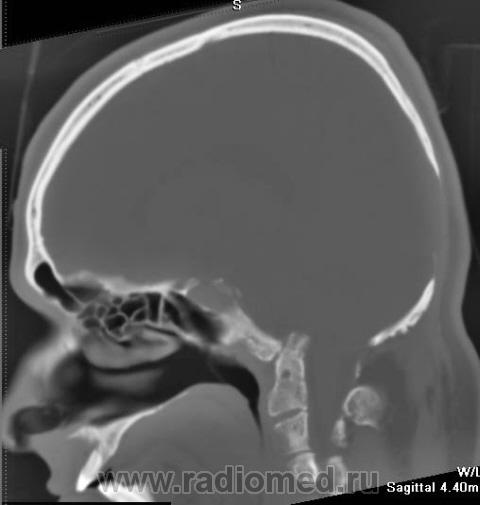

Nela. КТ головного мозга и костей. Гистиоцитоз Х (морфологическая верификация).

Пациент - молодой человек, предъявляет жалобы на головные боли и боли в шее. Болеет с 2002 года.

Гистиоцитоз Х – заболевание ретикулоцитарной системы неизвестной этиологии, морфологически характеризующееся первичной пролиферацией своеобразных гистиоцитов (клеток Лангерганса или клеток Х) и образованием в легких и в других органах и тканях гистиоцитарных гранулем и гранулематозных инфильтратов.

Заболевание относится к системным: гранулемы могут образовываться в различных органах, но наиболее часто поражаются легкие и кости. Заболевают чаще всего люди молодого возраста, между 20 и 40 годами, большей частьюмужчины.